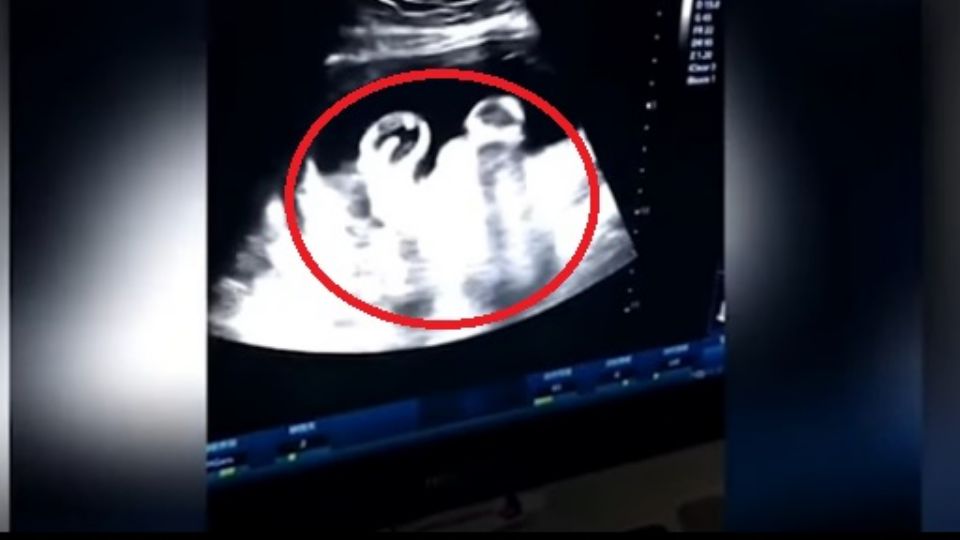

Gemelas se pelean en útero, padre capta el momento en video

por Redacción AM15 abril, 2019